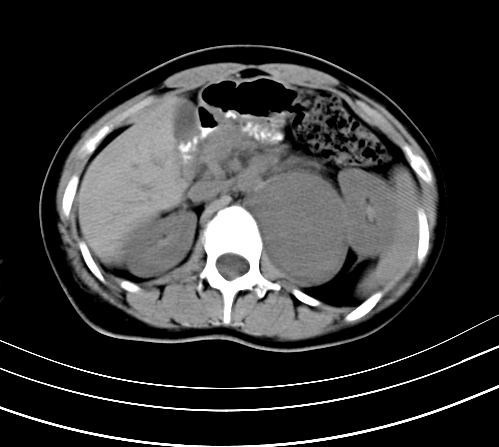

标题: CT23915:女 20岁 全身长疙瘩三年 今日多体位查 看看吧 [打印本页]

标题: CT23915:女 20岁 全身长疙瘩三年 今日多体位查 看看吧

腹部平扫

动脉期